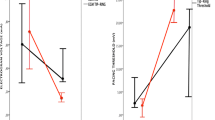

Both the intra- and interobserver variabilities for the measurement of DEPI (k = 0.97, k = 0.91, respectively) and ATOT (k = 0.95, k = 0.89, respectively) were low, indicating an excellent repeatability and reproducibility of the measurements. Samples showed a thickness of 4.36 ± 0.20 mm in SBB and 4.20 ± 0.20 mm in SUB, with no significant difference (p > 0.05). Transmural lesions were detected in 18 samples over 20 (90%) in SBB group, while in SUB, transmural lesions were present in 9 samples over 20 (45%) (Fig. 6).

The overall DMAX was significantly smaller in SBB than in SUB (1.62 ± 0.14 mm and 2.43 ± 0.30 mm, respectively; p < 0.05). Moreover, the DEPI and DENDO in SBB group (1.60 ± 0.14 mm and 1.59 ± 0.15, respectively) were smaller than DEPI and DENDO of SUB (2.28 ± 0.30 and 2.26 ± 0.40, respectively; all p < 0.05).

The ATOT in SBB was smaller than ATOT in SUB (521.97 ± 73.05 mm/mm2 and 581.01 ± 65.38 mm/mm2, respectively; p < 0.05). Likewise, the VTOT was smaller in SBB compared with SUB (52.19 ± 7.30 mm/mm3 and 58.10 ± 6.53 mm/mm3, respectively; p < 0.05).